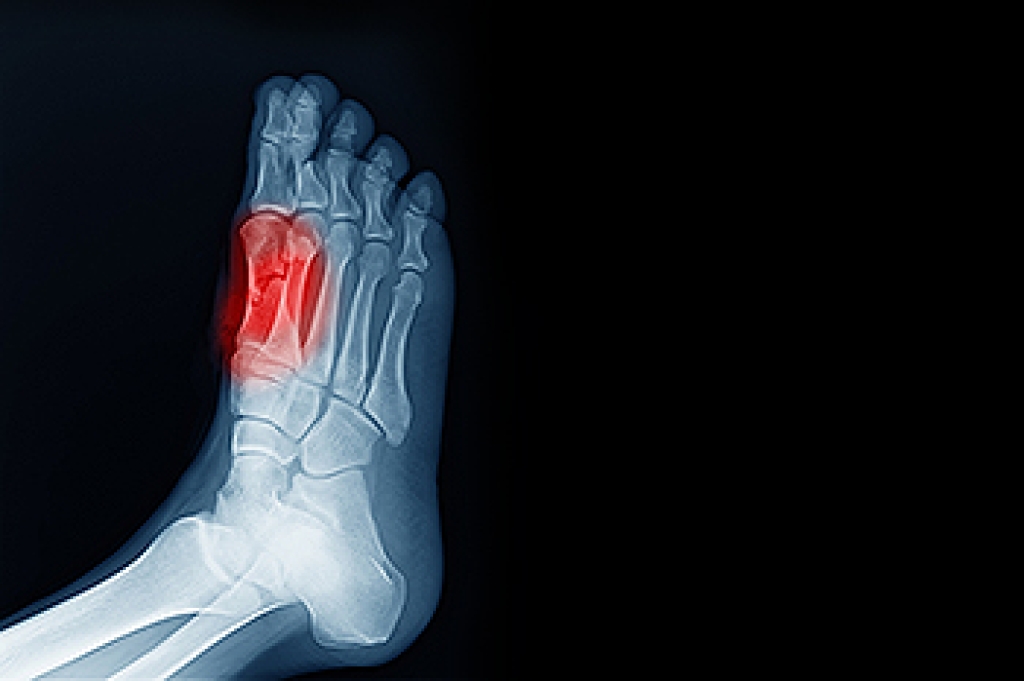

To figure out the cause of foot pain, podiatrists utilize several different methods. This can range from simple visual inspections and sensation tests to X-rays and MRI scans. Prior medical history, family medical history, and any recent physical traumatic events will all be taken into consideration for a proper diagnosis.

- Injury (from stress fractures, broken toe, foot, ankle, Achilles tendon ruptures, and sprains)